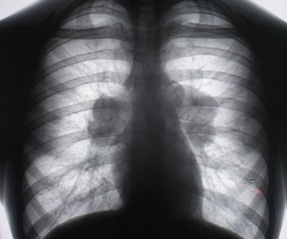

Цифровое стандартное флюорографическое профилактическое исследование (проведено на цифровом флюорографе «Ренекс – Флюоро»). На цифровых флюорограммах, произведенных в прямой, правой и левой боковых проекциях с обеих сторон определяется синдром двусторонней аденопатии. С обеих сторон определяется резкое увеличение и гомгенизация тени корней за счет резко гиперплазированных, в основном, бронхопульмональных лимфатических узлов с довольно чёткими, ровными контурами. Структура тени однородная. На фоне гиперплазированных лимфатических узлов чётко дифференцируются просветы главных бронхов.

Иллюстрации 1, 2, 3.

Рентгенологическое исследование, выполненное в апреле месяце 2008 г. выявило в грудной полости двустороннюю аденопатию за счет гиперплазии бронхо – пуцльмональных лимфатических узлов. Слева в области подмышечного сегмента нежное снижение прозрачности легочной ткани по типу «нежного пневмонита». Рентгенологических данных за объёмный процесс и полостное образование не выявлено. Выявлены изменения в крестце.